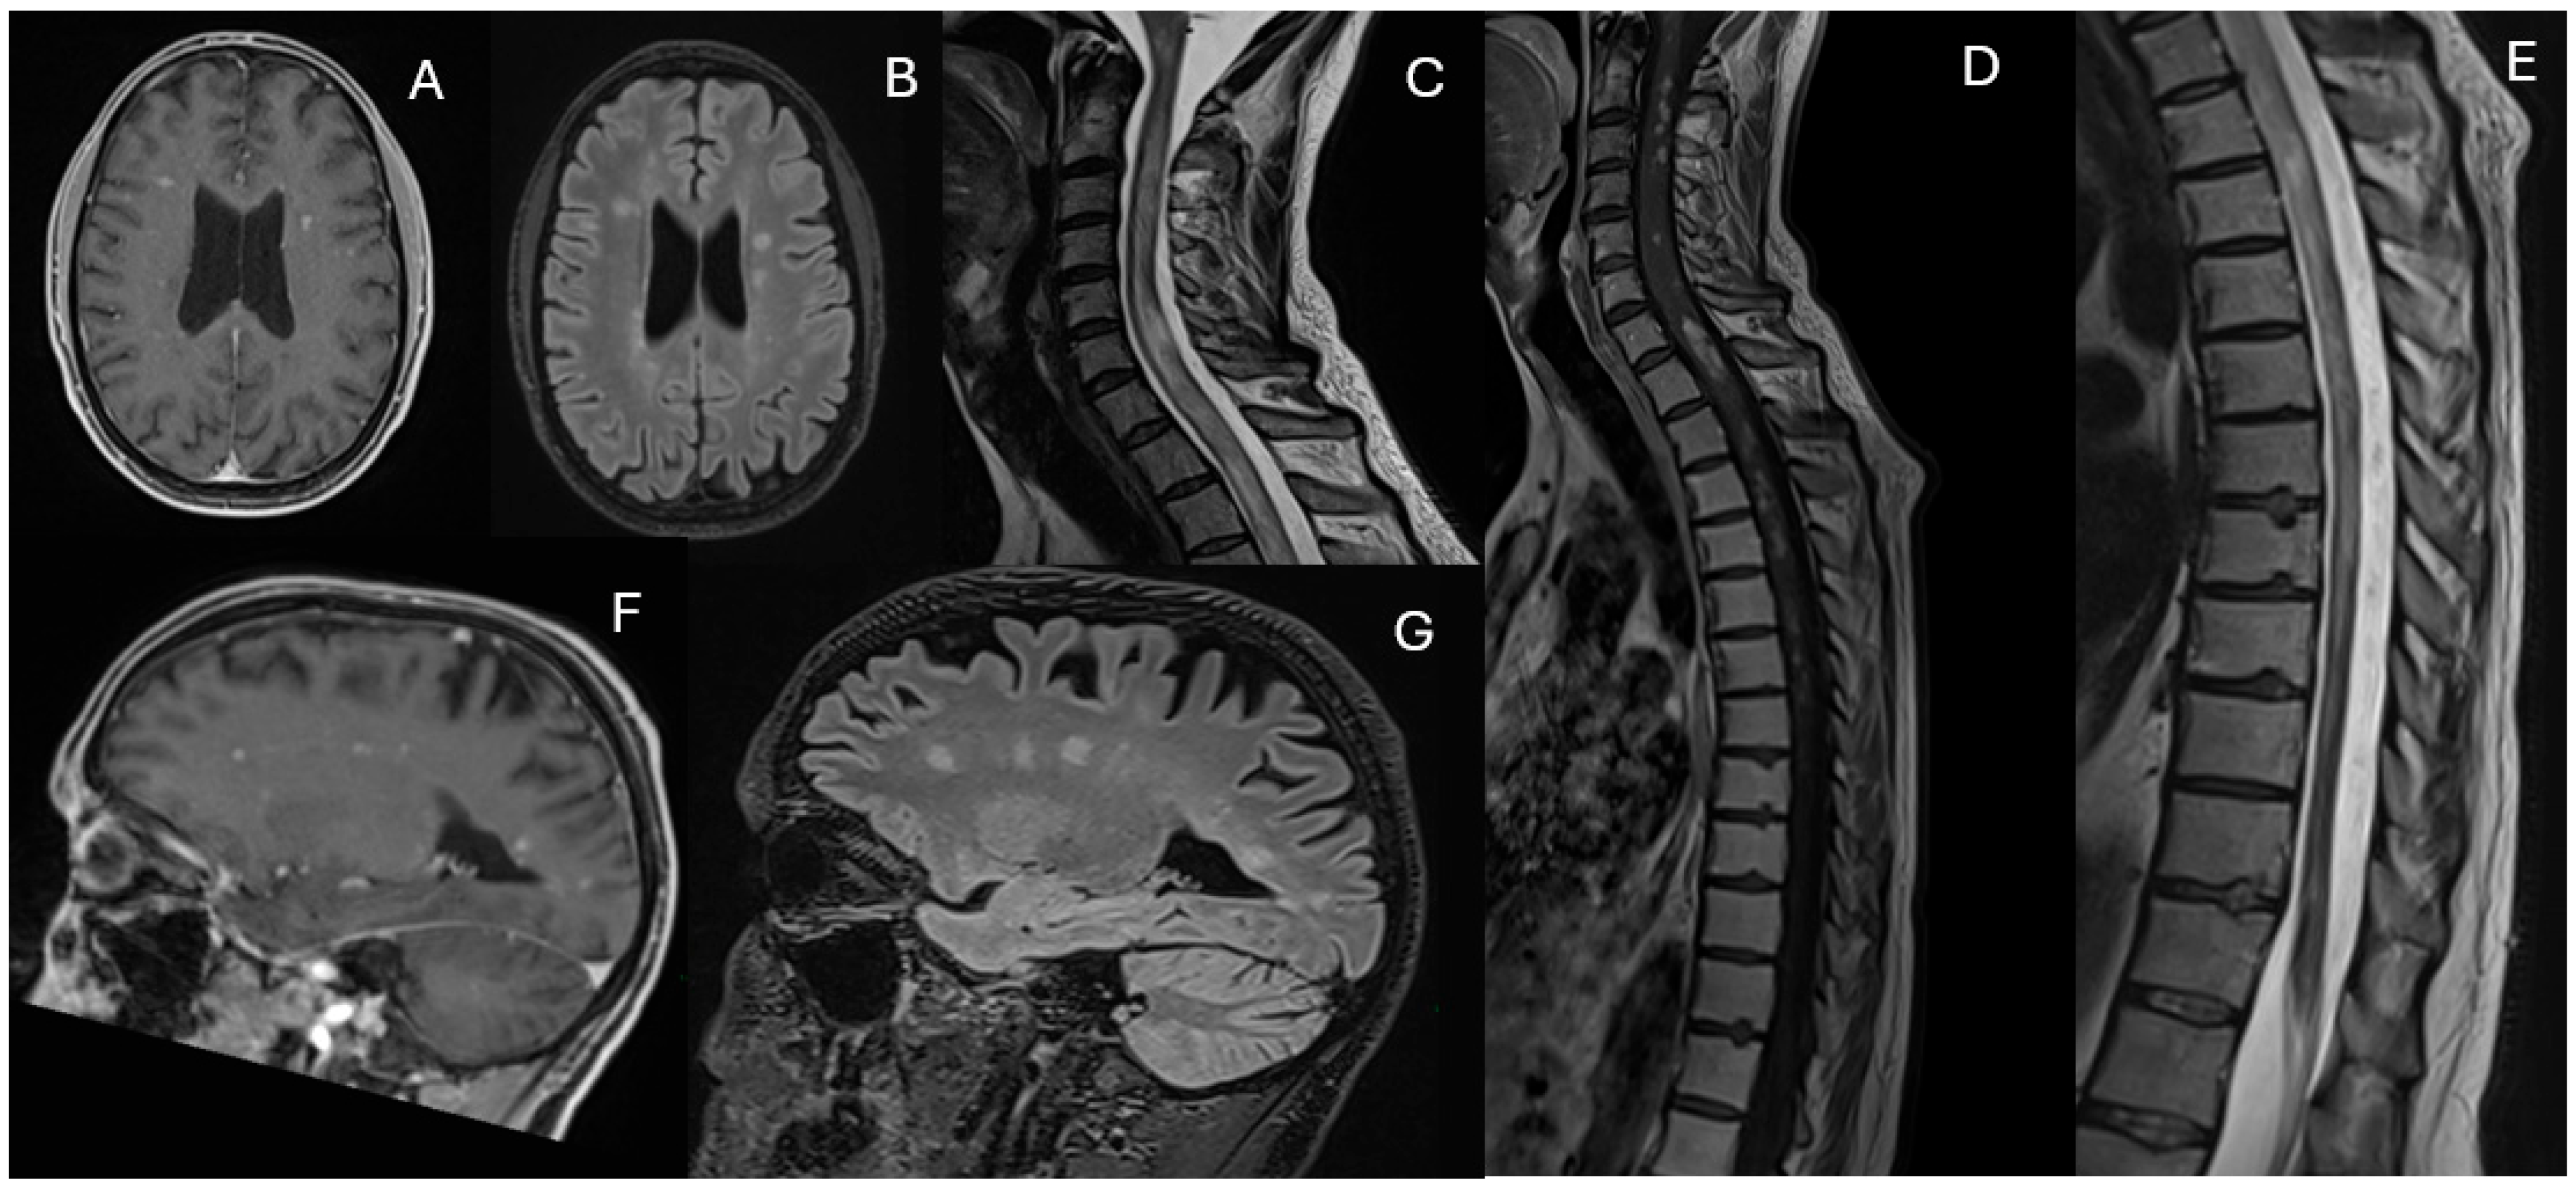

During the final hospitalization in March, follow-up MRI revealed early radiological signs of disease reactivation, without clear laboratory evidence of relapse (Figure 4).

Figure 4. Fluid-attenuated inversion recovery (FLAIR) (AD) (March 2025). The images show the appearance of a new hyperintense signal alteration on FLAIR in the right middle cerebellar peduncle and an increase in the hyperintense signal alteration on FLAIR in the right paratrigonal region.